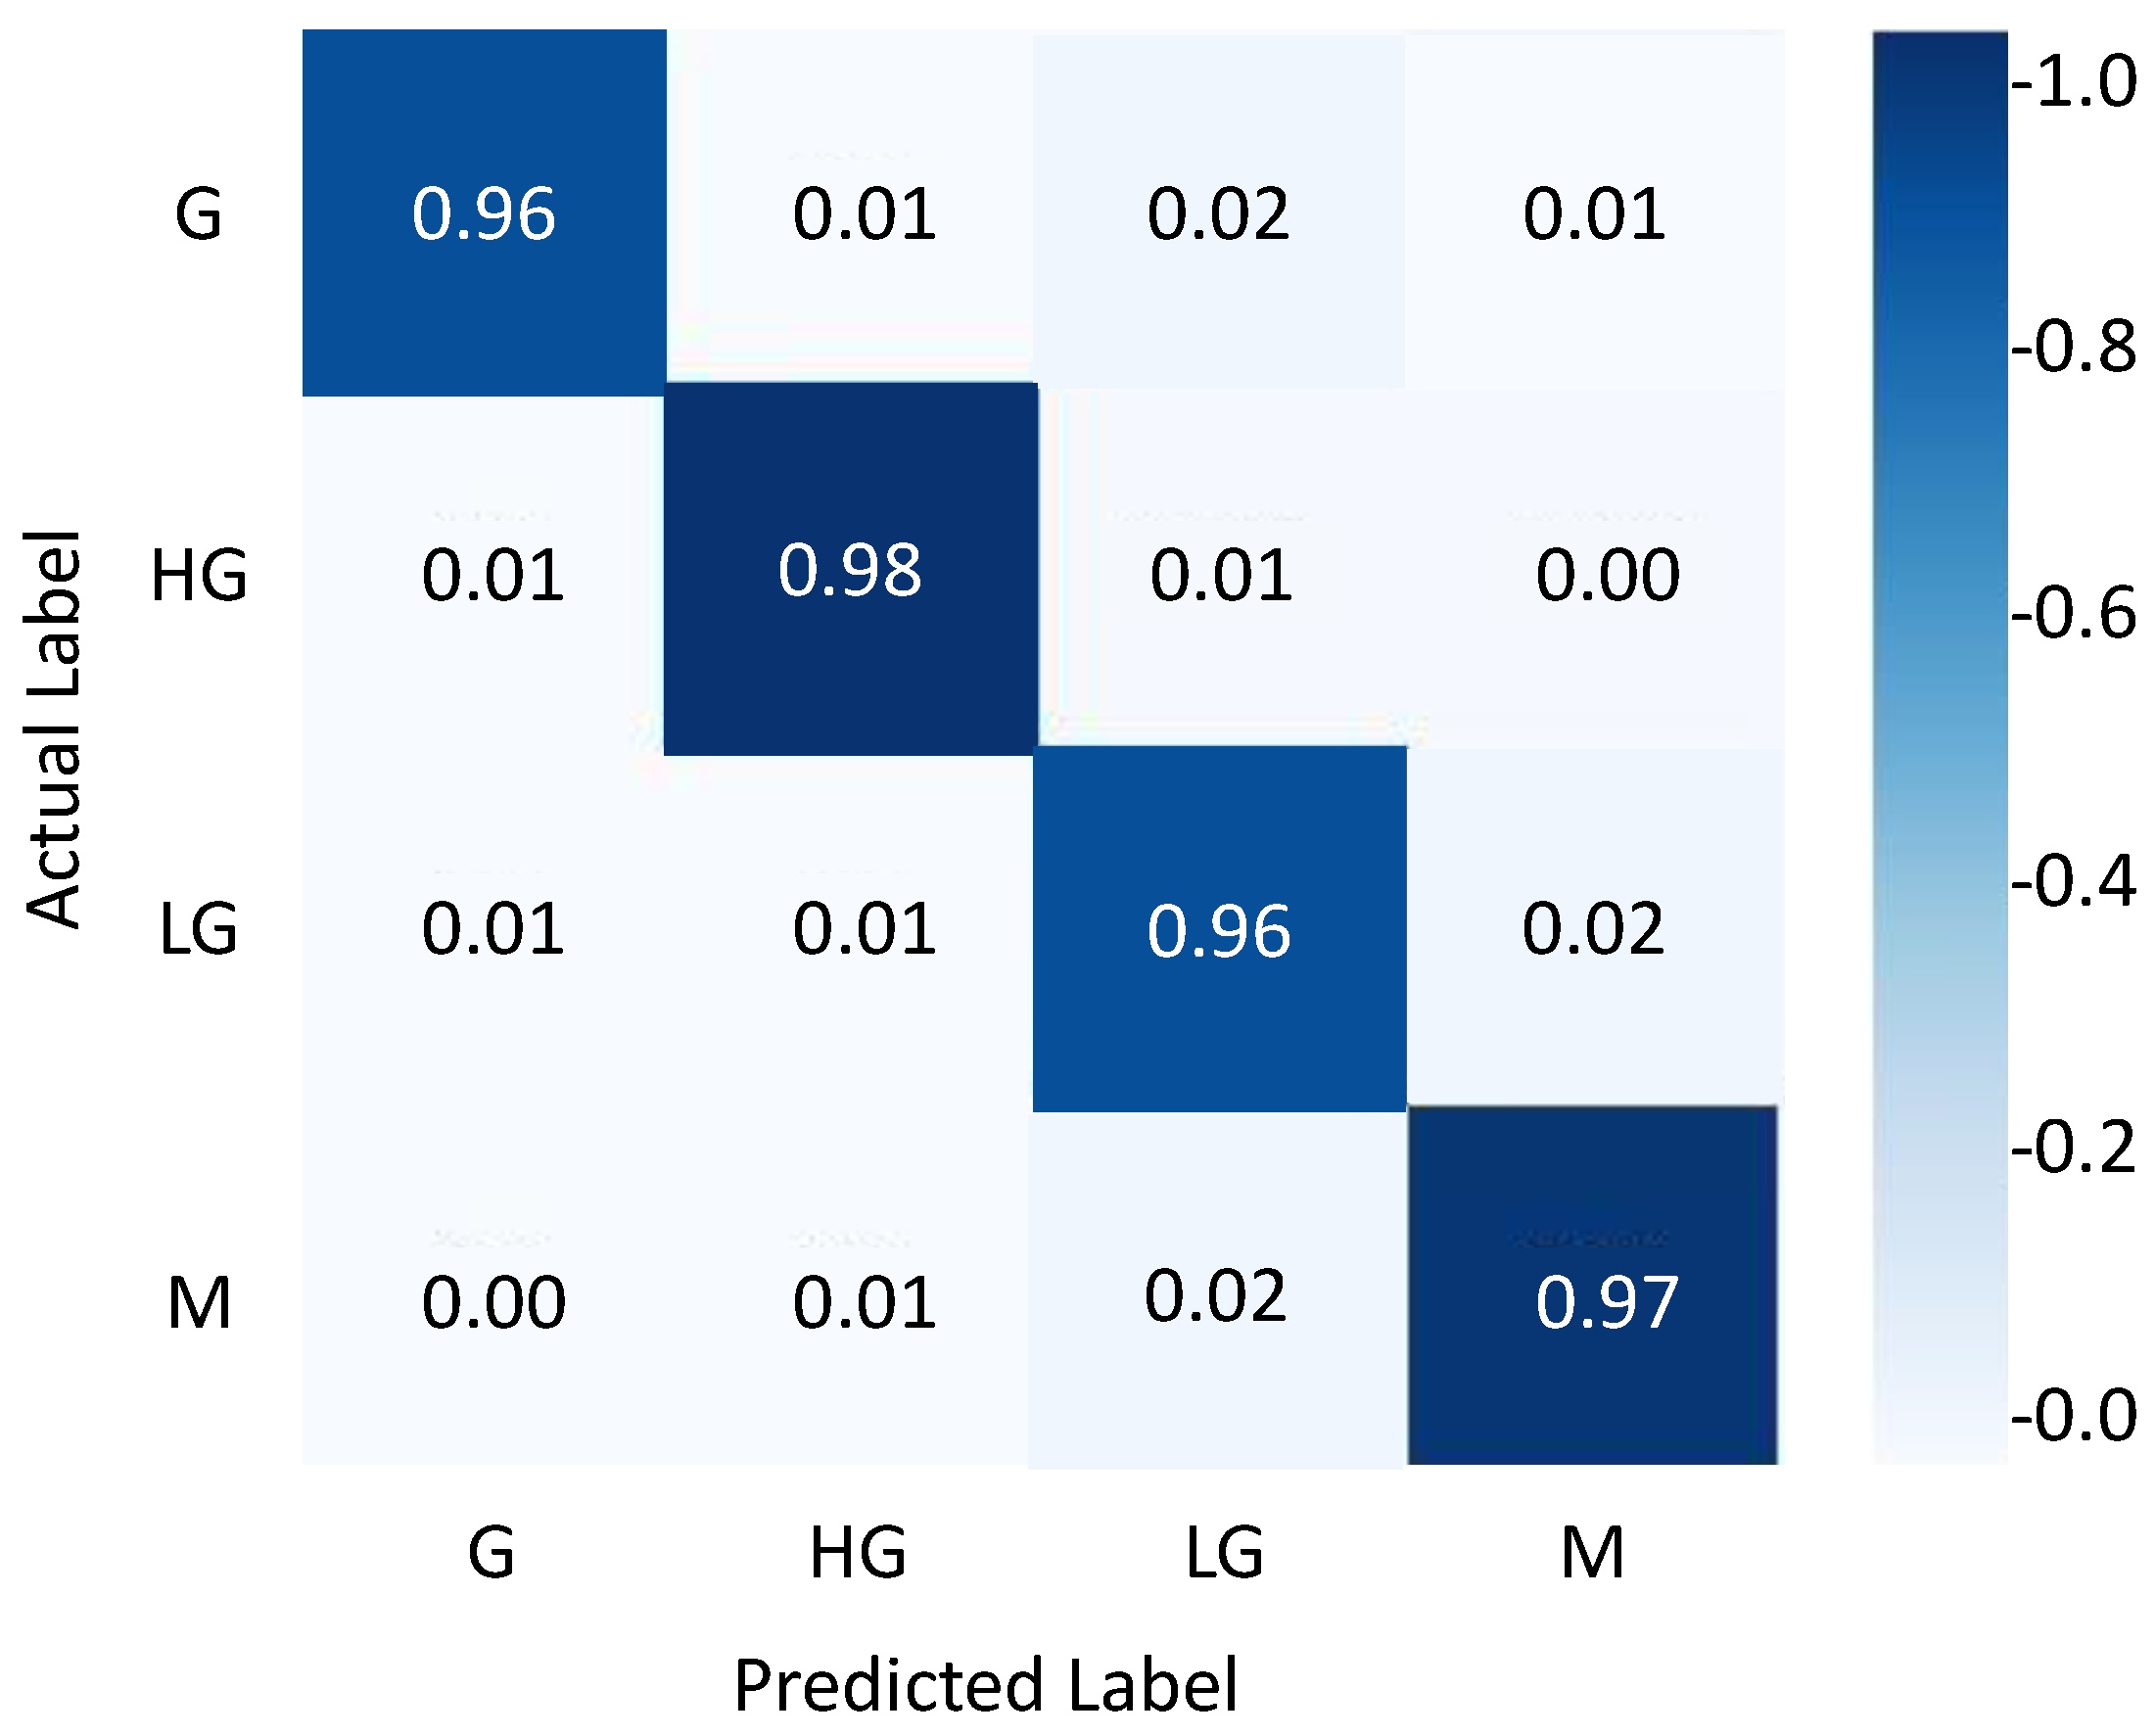

4.3. Results Evaluation Using BraTS 2018 Dataset

| Classes | Precision | Recall | F1-Score | Accuracy |

|---|---|---|---|---|

| G | 0.96 | 0.98 | 0.969 | 96.0 |

| HG | 0.98 | 0.97 | 0.974 | 98.0 |

| LG | 0.96 | 0.96 | 0.96 | 96.0 |

| M | 0.97 | 0.97 | 0.97 | 97.0 |

| Average | 0.967 | 0.970 | 0.968 | 96.75 |

| Approach | Accuracy |

|---|---|

| DR LBP features + k–NN [65] | 85.10 |

| Inception V3 + SVM [65] | 87.40 |

| PSO features + Softmax [65] | 92.50 |

| Two-Channel DNN [66] | 93.69 |

| Proposed model | 96.75 |